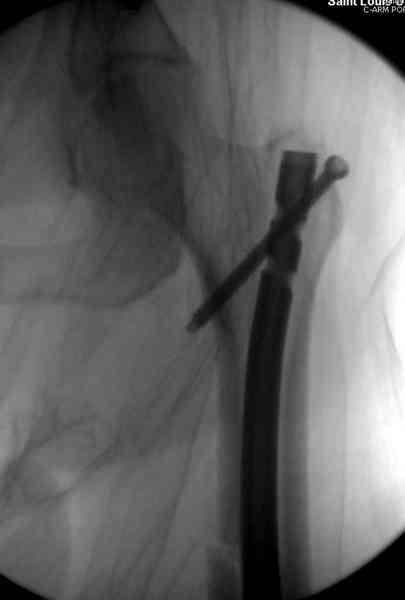

В первый же день произведено антеградное штифтованием DePuy Trochanteric Nail.

На второй день (7) обнаружен пропущенный перелом,

и проведены шурурпы через и спереди штифта без удаления.